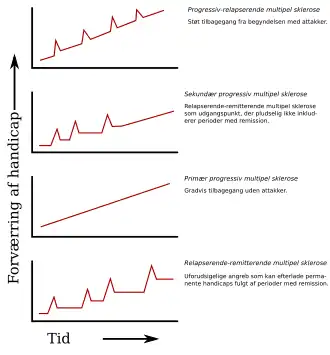

Flere typer af sygdommen, eller mere præcist mønstre for sygdommens forløb, er blevet beskrevet. Når typen skal fastlægges, benytter man sig af udviklingen hidtil med det formål at forudsige det videre forløb. Det er vigtigt at fastslå typen, ikke blot for at kunne opstille prognoser men også for at kunne beslutte, hvordan sygdommen skal håndteres. I 1996 standardiserede USA's National Multiple Sclerosis Society de fire typers definitioner:[7]

- relapserende-remitterende,

- sekundær progressiv,

- primær progressiv og

- progressiv relapserende.

Den relapserende-remitterende type er karakteriseret ved uforudsigelige attakker efterfulgt af perioder på måneder eller år, hvor sygdommen forholder sig nogenlunde rolig (remission) uden nye tegn på sygdomsaktivitet. Problemer opstået under angreb kan enten forsvinde eller efterlade følgesygdomme, hvor det sidstnævnte dog er mere almindeligt som en funktion af tid.[1] 85-90% af alle patienter med MS, har et begyndende sygdomsforløb, der kan beskrives af den relapserende-remitterende type.[7] Når problemerne altid forsvinder mellem attakker, kaldes typen nogle gange for godartet MS.[37] Den relapserende-remitterende type begynder som regel med et klinisk isoleret syndrom (CIS). I CIS har patienten angreb, der tyder på demyelinering, men opfylder ikke alle kriterierne for MS.[1][38] Dog udvikler kun 30 til 70% af personer, der oplever CIS, MS.[38]

Sekundær progressiv MS beskriver omkring 65 % af de, der indledningsvist har haft relapserende-remitterende MS, men som begynder at have progressive neurologiske problemer mellem akutte angreb uden nogen egentlig periode med remission.[1][7] Lejlighedsvise tilbagefald og mindre remissioner kan forekomme.[7] Den gennemsnitlige tid mellem sygdommens udbrud og ændring fra relapserende-remitterende til sekundær progressiv MS er 19 år.[39]

Den primære progressive type beskriver de cirka 10–15%, der aldrig oplever remission efter deres første MS-symptomer.[40] Typen er karakteriseret ved progression af handicap helt fra sygdommens udbrud med ingen eller kun lejlighedsvise remissioner og forbedringer.[7] Alderen, hvor man rammes af den primære progressive type, er højere end ved den relapserende-remitterende, men lignende gennemsnitsalderen for overgangen fra den relapserende-remitterende til den sekundære progressive type. I begge tilfælde er det omkring fyrreårsalderen.[1]

Progressiv relapserende MS beskriver de personer, der fra start oplever støt neurologisk tilbagegang, men lider af klare angreb oveni. Dette er den mindst almindelige af alle MS-typerne.[7]